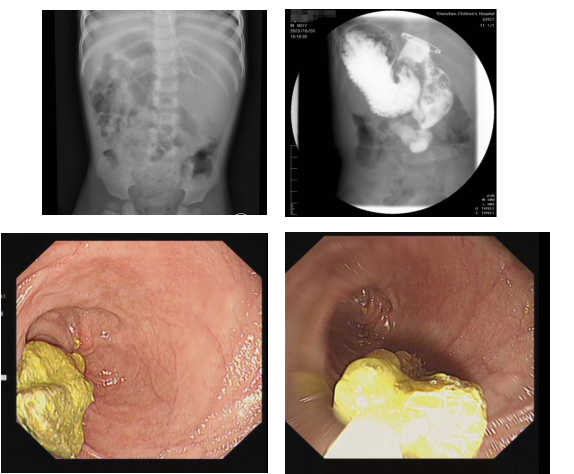

收治入院后,我院内镜中心代东伶主任团队高度重视。通过精细化的上消化道造影和内镜检查,迅速明确了病因:十二指肠降段严重狭窄,且有一枚约2cm的异物嵌顿于狭窄段上方。这一精准诊断,为后续的微创治疗奠定了坚实基础。

面对患儿复杂的腹腔情况和高风险,在多学科协作下,代东伶主任领衔的内镜团队制定了周详的内镜介入方案。在麻醉科胡一副主任医师的精准护航下,手术团队首先在内镜下顺利取出异物,随后运用三级球囊扩张导管,对坚硬的狭窄环进行分级、可控的扩张,成功撕裂狭窄环,瞬间疏通了梗阻的肠道。为确保术后恢复,团队还成功置入了鼻空肠营养管。普外科毛建雄主任的全程在场,为内镜团队提供了强大的信心支持,使得团队能够果断、从容地处理狭窄问题。最终,内镜手术大获成功,整个手术微创、精准、高效,避免了外科开腹手术。